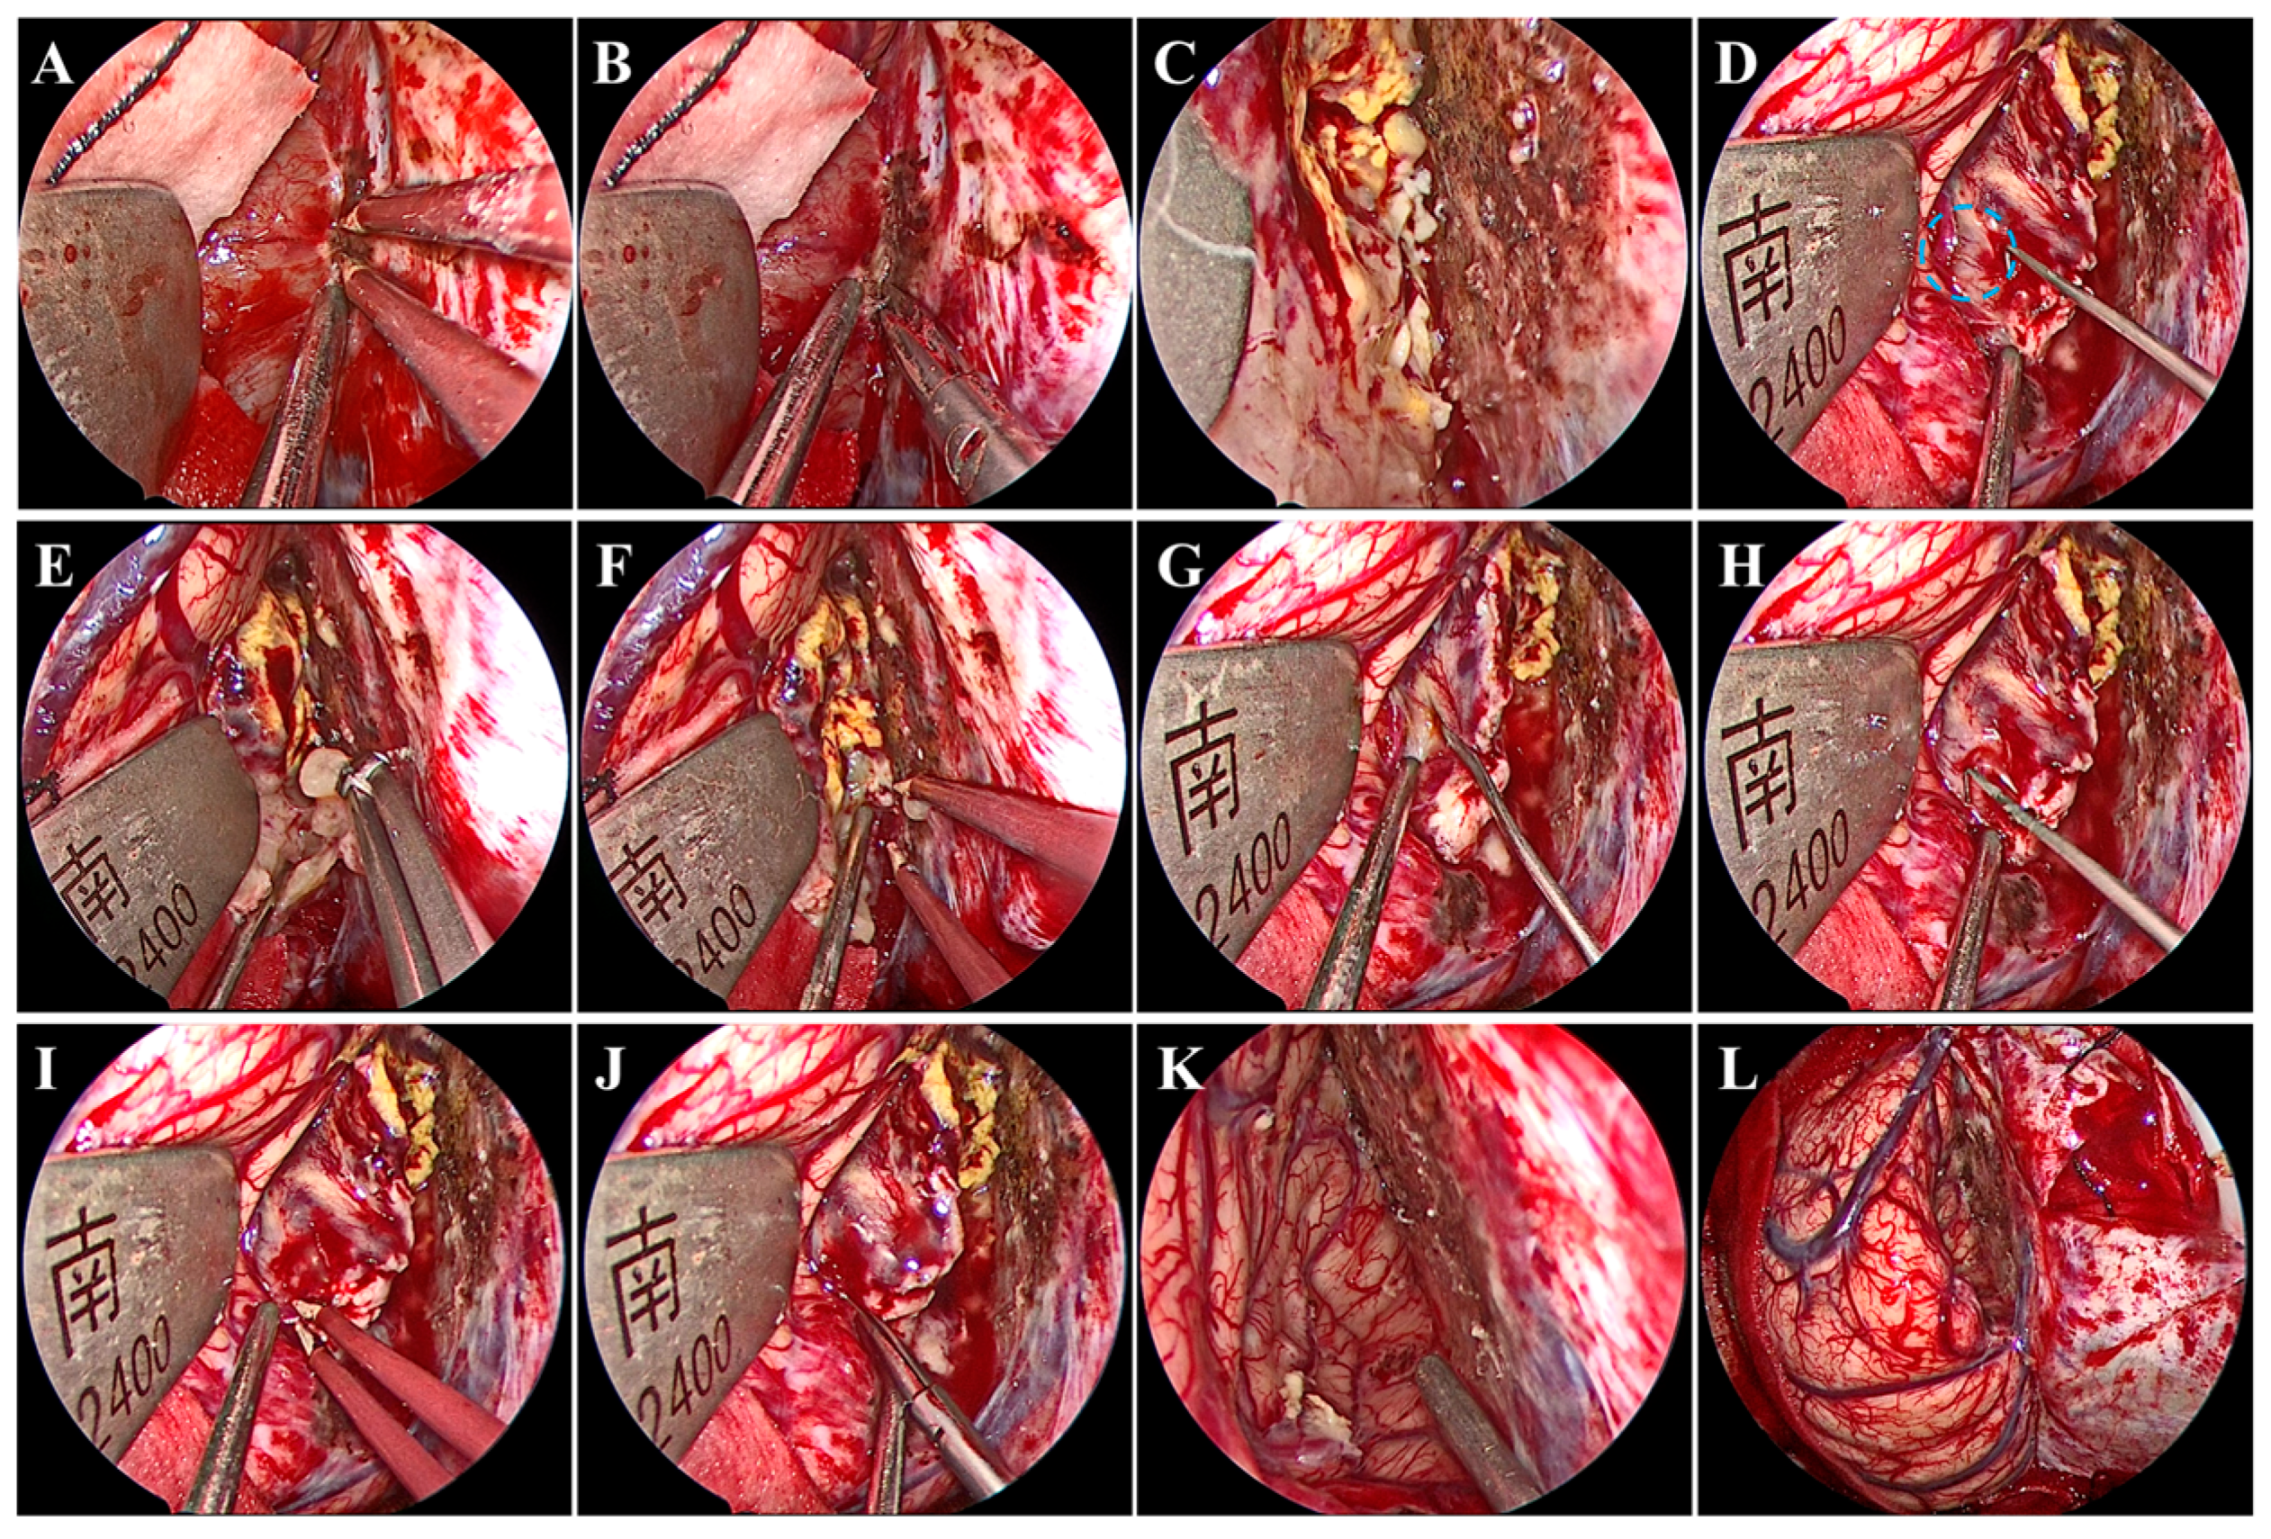

Under general anesthesia by endotracheal intubation, the patient was placed in the supine position. The head was fixed using a head clamp with no rotation. A horseshoe-shaped incision was made to expose the skull after identifying the location of appropriate craniotomy using neuronavigation. Next, a hole was drilled on the lateral edge of the superior sagittal sinus (SSS), and a 7 cm × 6 cm craniotomy was made. Particular caution should be taken to avoid damage to the SSS and bridging veins from dural laceration. After the removal of the bone flap, a radial incision was made on the dura mater with its base toward the SSS. Twenty minutes before the dura mater was opened, mannitol was administered to decrease the intracranial pressure. We introduced the endoscope following dural mater incision. A hand-held endoscope is often used to observe the tumor and develop a resection plan. A pneumatic arm holds the endoscope in one corner while the surgeon conducts bimanual surgery to remove the tumor. Subsequently, under endoscopic visualization, the arachnoid adhesions over the SSS were freed, while the bridging veins above the tumor were not. Notably, brain retraction was kept to a minimum. The falx was then separated to access the tumor in the depths. Once the tumor was visualized, electrocautery and dissection of the tumor base were performed using bipolar forceps and microscissors to block the blood supply from the falx (Figure 2A,B). After the treatment of the tumor base, the tumor was still bleeding (Figure 2C), which suggested that the tumor had an additional blood supply from the cerebral cortex (Figure 2D). Next, the tumor was internally resected in a piecemeal fashion with an aspirator and tumor-grasping forceps (Figure 2E,F). An adequately thick margin should be left to avoid damage to the cerebral cortex and to facilitate subsequent dissection of the tumor envelope. Subsequently, under endoscopic visualization, the tumor envelope was carefully dissected and separated from the surrounding cerebral cortex to remove the remaining tumor shell, all of which was performed with good visualization (Figure 2G–J). During this procedure, there was one area where the tumor tissue was tightly adherent to the cortical artery and extremely difficult to separate. Therefore, the tumor tissues around the artery were removed in a piecemeal manner and properly fulgurated, retaining a thin slice of the tumor (Figure 2K). Gross total tumor resection was ultimately achieved without damage to the bridging veins, and accurate hemostasis was verified under endoscopic visualization (Figure 2K,L). The major surgery process is presented in Video S1. Although it is easy to achieve a Simpson I resection after gross total tumor resection, in our procedure, instead of removing the cerebral falx at the base of the tumor, a fulguration was performed to preserve the falcine venous plexus (Simpson II). Finally, the dura mater was tightly sutured; the bone was secured using mini plates; and the skin incision was closed. The procedure took 253 min.

Figure 2.

Intraoperative endoscopic views. Treatment of the tumor base with bipolar forceps (A) and microscissors (B). (C) Continued bleeding of the tumor. (D) Small anastomosing vessels (blue circle) between the drainage veins of the cerebral cortex and the tumor. Internal resection of the tumor using tumor-grasping forceps (E) and an aspirator (F). Dissection and separation of the tumor envelope using nerve strippers (G,H), bipolar forceps (I), and microscissors (J). Accurate hemostasis was verified (K) without damage to the bridging veins (L).